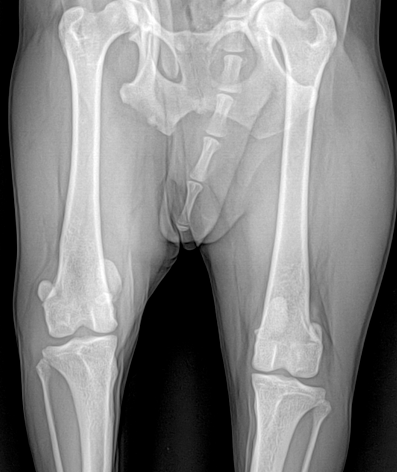

고관절 이형성증(Hip displasia) 및 대퇴골두 무혈성 괴사(LCPD)

고관절 이형성증과 대퇴골두 무혈성 괴사는 반려동물에서 고관절의 비정상적인 형성과 혈액 공급 장애로 인해 심한 통증과 운동 장애를 일으키는 질환입니다. 본원에서는 정확한 진단과 함께 대퇴골두 절제술(FHNO) 등 적절한 수술 치료를 통해 통증 완화와 기능 회복을 목표로 합니다.